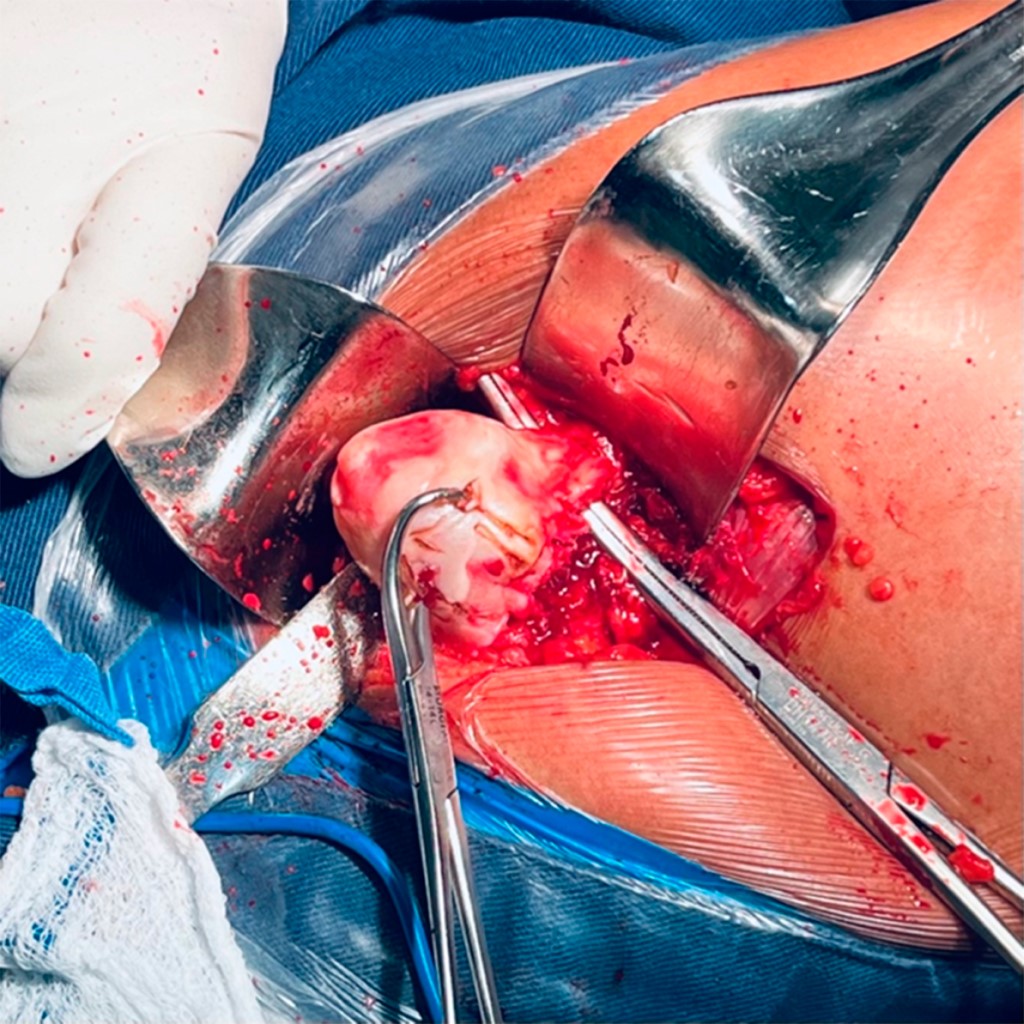

Con la paciente bajo anestesia regional y previa profilaxis antibiótica, se coloca en posición de cubito lateral derecho. Por anatomía de superficie se identifican referencias anatómicas: trocánter mayor y diáfisis femoral. Se realiza un abordaje lateral directo de Hardinge, disección por planos aplicando hemostasia con electrocauterio, se hace un corte longitudinal de fascia lata con tijera de Metzenbaum; se efectúa colgajo muscular de glúteo medio y menor (Figura 2); posterior a esto, capsulotomía en T invertida, para identificar cabeza femoral y realizar osteotomía a 10 mm por arriba del trocánter menor; se identifica ligamento redondo (Figura 3), con el fin de diseccionar hasta su origen sobre la escotadura y localizar el acetábulo nativo, retirando tejido blando remanente de cápsula articular (Figura 4).

Figura 3